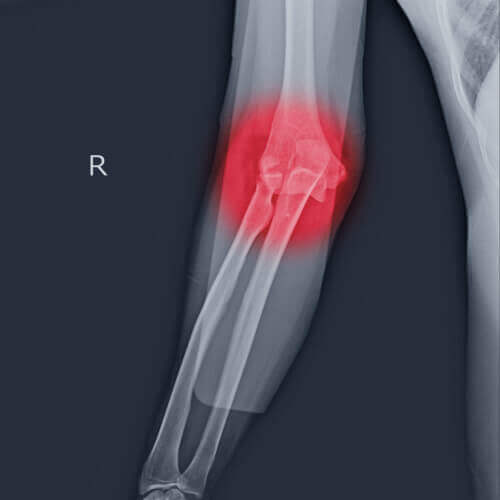

The Elbow is a complex hinge joint formed by the articulation of three bones – humerus, radius and ulna. The upper arm bone or humerus connects the shoulder to the elbow forming the upper portion of the hinge joint. The lower arm consists of two bones, the radius and the ulna. These bones connect the wrist to the elbow forming the lower portion of the hinge joint.

The three joints of the elbow are

• Ulnohumeral joint, the junction between the ulna and humerus

• Radiohumeral joint, the junction between the radius and humerus

• Proximal radioulnar joint, the junction between the radius and ulna